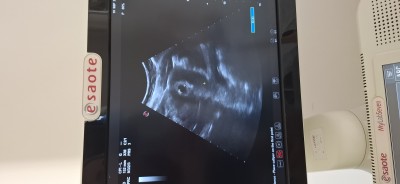

Kızlarr son adet tarihim 31 temmuz son adete göre 6 haftalık ama bugun randavum vardı doktor keseyi yolk kesesini gördü ama bebeği göremedi telaşlandım başına böyle bişey ggelen varmı ben bu ultrasonda yolk kkesesinide görmüyorum  sizce görüyormusunzz?

Gebelik haftası 5+3